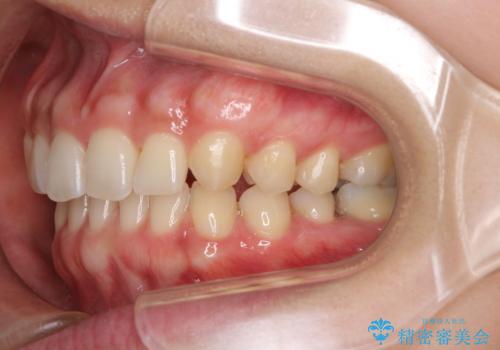

- 前歯の隙間と奥歯の目立つ銀歯を気にして来院された患者様です。

インビザラインにより下顎前歯の隙間を閉じるとともに、奥歯の咬み合わせを改善させることとしました。

矯正治療後には、銀歯のクラウンをセラミッククラウンへ替える補綴治療を行うこととしました。